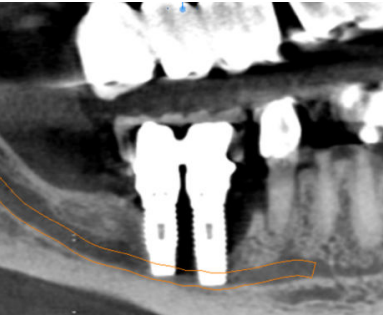

Considerando las características del caso, se realizó en un primer tiempo la exodoncia del diente 45 y la explantación de ambos implantes, además de eliminar el proceso infeccioso subyacente. La intervención y el postoperatorio transcurrieron con normalidad y el paciente recuperó la sensibilidad del labio durante el mes siguiente a la intervención. Cuatro meses después de la cirugía inicial, se solicitó un nuevo CBCT para valorar el defecto óseo remanente (Figura 2).